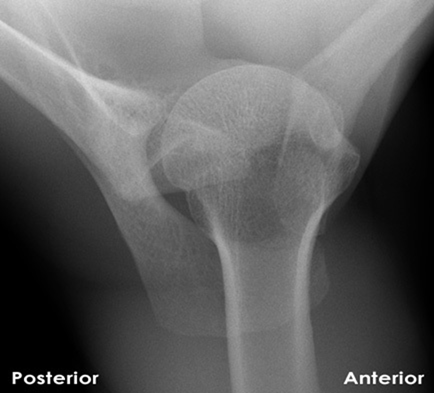

Question 10:

A 70-year-old male sustains an anterior shoulder dislocation. After reduction, plain radiographs show a concomitant fracture. Which fracture is MOST commonly associated with anterior shoulder dislocation in this age group?

Correct Answer: Greater tuberosity fracture

Explanation:

While Hill-Sachs and Bankart lesions are very common with anterior dislocations, in older patients, a greater tuberosity fracture is particularly common (up to 30% in some series) due to the weaker bone and the forces involved in the injury. The rotator cuff avulses a piece of the tuberosity during the dislocation. Surgical neck fracture is also possible but less frequent than greater tuberosity in direct association with dislocation. Clavicle fractures are less directly associated with glenohumeral dislocation mechanism.

Question 30:

A 45-year-old male sustains a fall onto his abducted arm. Radiographs confirm an anterior shoulder dislocation. Which associated fracture is most likely due to impaction of the posterior-superior humeral head against the anterior glenoid rim?

Correct Answer: Bony Bankart lesion

A Bony Bankart lesion is an avulsion fracture of the anterior-inferior glenoid rim, occurring when the humeral head dislocates anteriorly and impacts the glenoid. A Reverse Hill-Sachs lesion is associated with posterior dislocations. Greater tuberosity and surgical neck fractures are also associated but are different mechanisms. Clavicle fractures are less directly associated with the dislocation mechanism itself.

What is the primary significance of a 'Hill-Sachs lesion' in the context of shoulder dislocation?

Correct Answer: It is an impaction fracture on the posterior-superior aspect of the humeral head, typically associated with anterior dislocation.

A Hill-Sachs lesion is an impaction fracture on the posterior-superior aspect of the humeral head, caused when the humeral head impacts against the anterior glenoid rim during an anterior dislocation. It is a key indicator of prior anterior dislocation and contributes to recurrent instability. Reverse Hill-Sachs is for posterior. Greater tuberosity is a separate fracture. Rotator cuff tears and labral tears are distinct injuries.